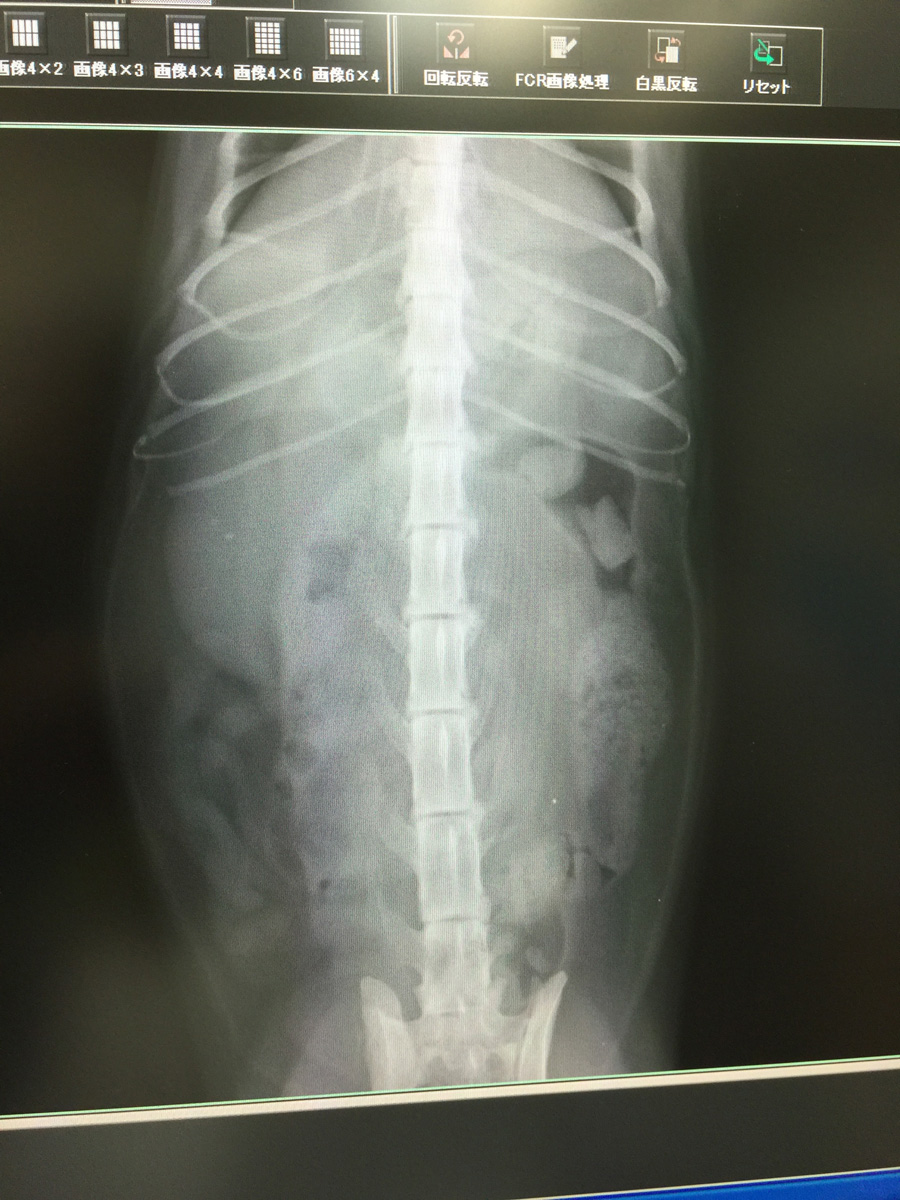

うおっほ、これがだいずさんのレントゲン写真です

これがだいずさんの右の腎臓です

いや全く無い訳ではありませんが3年前の写真と比べると明らかに左側が萎縮してます

その代わり動いている右側が肥大してフル稼働しているようです

だいずさんは生まれ付き左側の腎臓が機能不全と考えられます